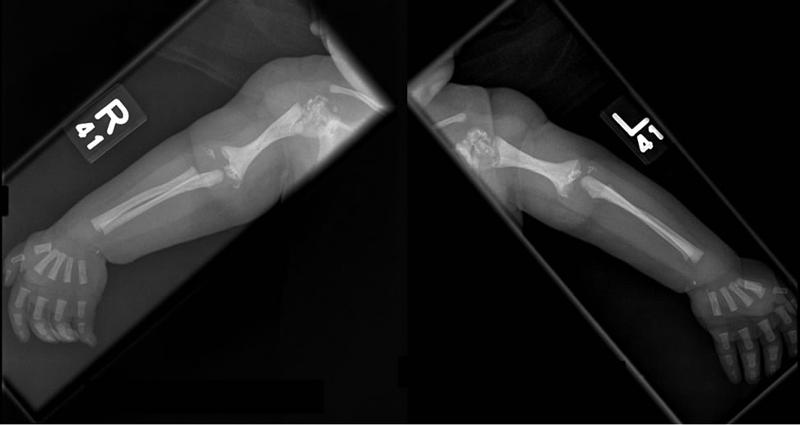

What is Rhizomelic shortening?

Shortening of proximal limb segment

Rhizomelia

Rhizomelia

What bones can be Rhizomelic ?

femur

humerus

When can rhyzomelia be diagnosed in utero?

by femur length

27 - 30 weeks

measurement of femur length starts dropping off